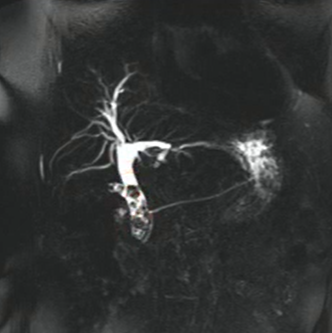

Quem sou eu?

A

CPRE

10

Q

Colangioressonância